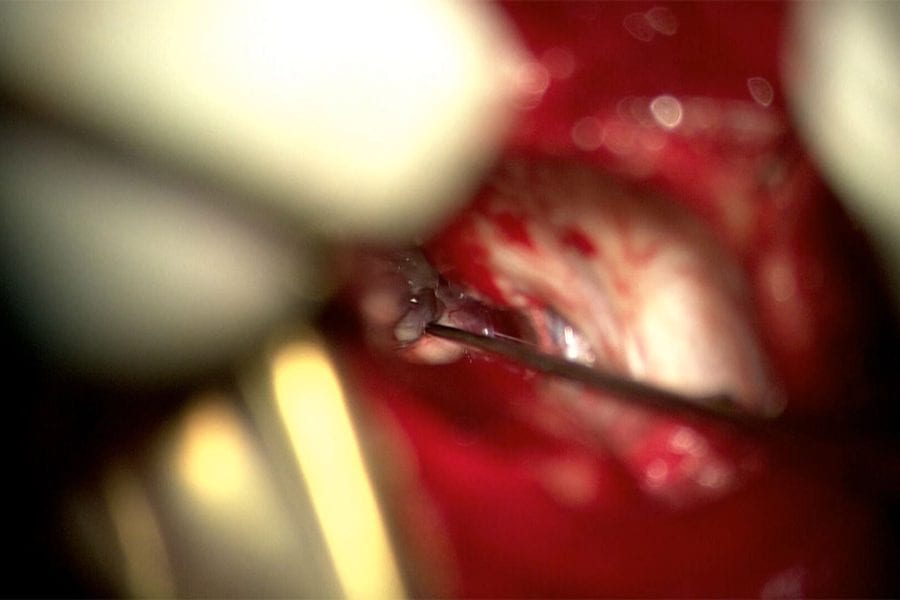

The patient in this video had severe sciatica due to nerve root compression. Surgery was performed to decompress the nerve.

In the video we show drilling of the lamina, and using a Kerosen Rongeour upcut to carefully bite away bone and ligament. A blunt hook is used to mobilise the nerve and to feel around the nerve to ensure it has been fully decompressed. This patient woke up well, with no leg pain, and returned to his usual activities within a few weeks. He is very happy with his results.